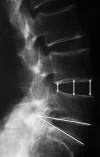

The ligamentum flavum is considered to be one of the important causes of radiculopathy in lumbar degenerative disease. Although there have been several reports anatomically examining the positional relationship between the ligamentum flavum and nerve root, there are few reports on ventral observation. The purpose of this study is to clarify the shape of the ligamentum flavum seen ventrally, and to obtain anatomic findings related to nerve root compression. The subjects were 18 adult embalmed cadavers, with an average age of 78 years at the time of death. The ventral shapes of the ligamentum flavum were observed. The relationships between the morphological change of the ligamentum flavum and nerve root compression or radiographic findings were statistically evaluated. Among the shapes of the ligamentum flavum, bulging of the ligament was most frequently observed. Proximal bulging indicates the type with the cranial portion bulging from the subarticular zone to the foraminal zone of the ligamentum flavum. In this type associated with a decrease in disc height, nerve root compression was frequently observed. Thus, we could more realistically grasp the relationship between bulging morphology of the ligamentum flavum and nerve root compression.